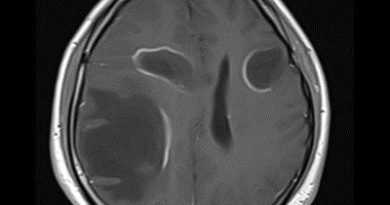

60 yaş, K

Baş ağrısı

Tanınız nedir?